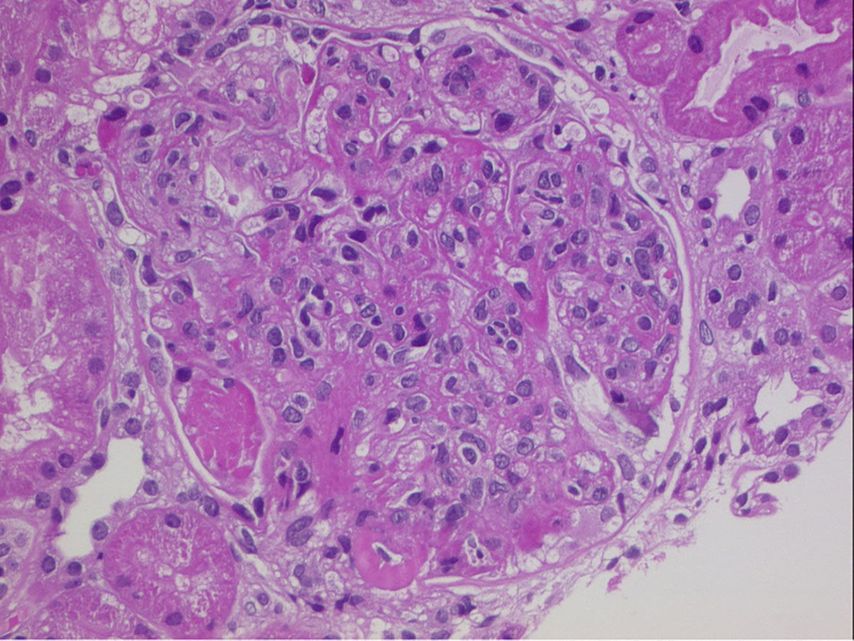

Abb. 1: HE-Färbung: Glomerulum mit typischen Veränderungen einer proliferativen Lupusnephritis (mesangiale und endokapilläre Hyperzellularität, subendotheliale Depots und hyaline Thromben)